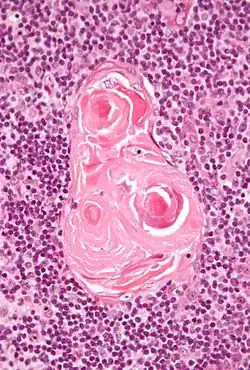

Ciałka Hassalla

Ciałka Hassalla – drobne, kuliste struktury, obecne tylko w części rdzennej grasicy, utworzone przez zdegenerowane i zebrane w grupy komórki nabłonkowe. Pojawiają się już w życiu płodowym, a ich liczba wzrasta do okresu dojrzałości płciowej[1]. Ich funkcja nie jest w pełni znana. Prawdopodobnie mogą być miejscem rozpadu limfocytów oraz zachodzenia procesów wydzielniczych grasicy. Opisał je Arthur Hill Hassall w 1849 roku[2].

Zbudowane z koncentrycznie ułożonych, spłaszczonych komórek nabłonkowych, wykazujących często cechy rogowacenia. Komórki tych ciałek produkują cytokiny i współpracując z obecnymi w rdzeniu komórkami dendrytycznymi indukują różnicowanie się limfocytów Treg[3].